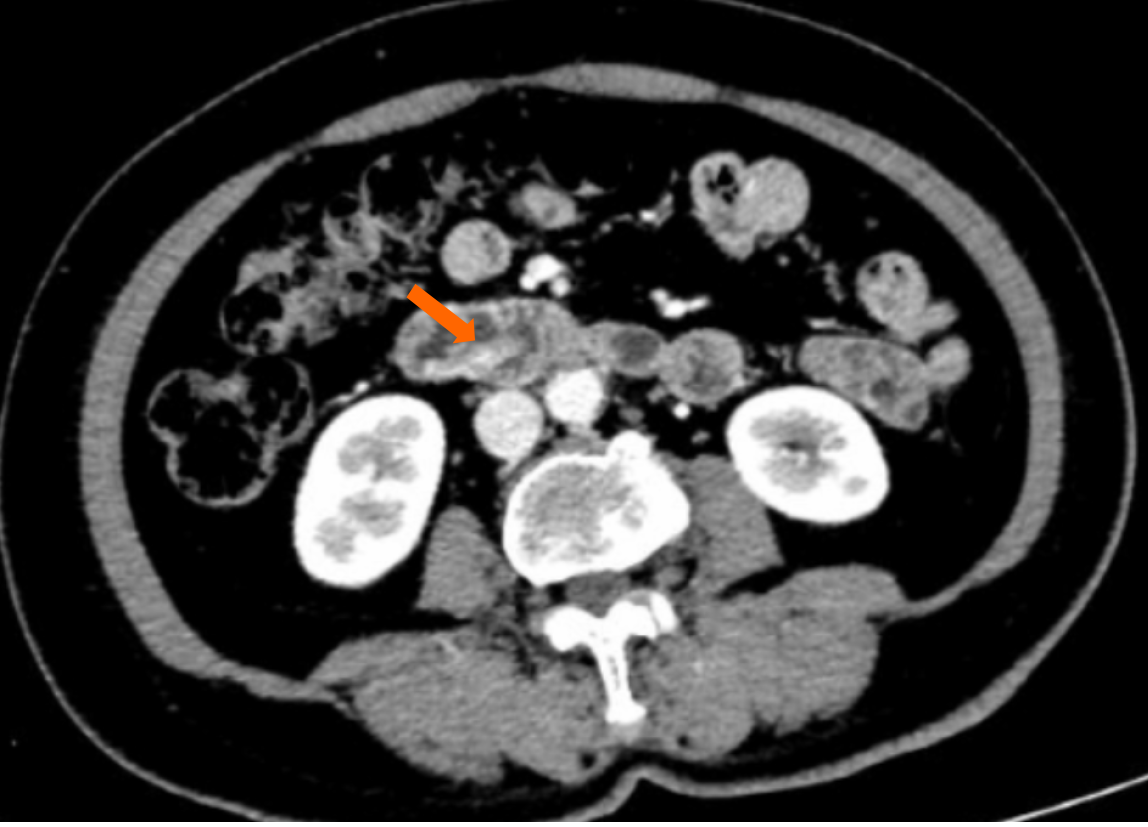

Abdominal computed tomography revealed a strip-like soft tissue density lesion in the descending portion of the duodenum, measuring approximately 10 cm in length. The lesion exhibited mild to moderate enhancement on contrast-enhanced imaging, suggesting a subepithelial origin (Figure 1). Fifteen months earlier, upper endoscopy had identified a mucosal elevation measuring approximately 1.5 cm in diameter in the second portion of the duodenum (Figure 2A). On repeat endoscopy, the lesion had significantly enlarged, appearing as a 10-cm slender, elongated, pedunculated mass with a smooth surface, arising from the duodenal mucosa (Figure 2B and C). Narrow band imaging did not reveal any adenomatous or suspicious features (Figure 2D). This indicated rapid growth over a relatively short period of 15 months, raising clinical concern despite the typically benign nature of such lesions.